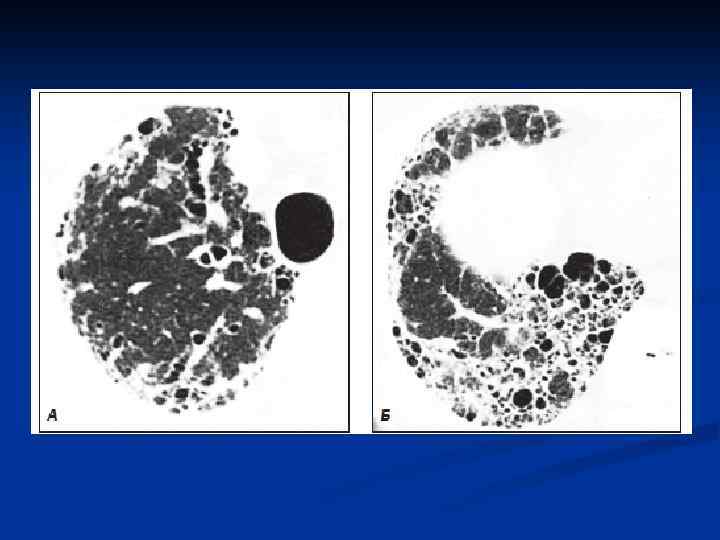

Различают 5 степеней патоморфологических изменений в легочной ткани у больных идиопатическим фиброзирующим альвеолитом: n n n I степень: отек межальвеолярпых перегородок, клеточная инфильтрация, извилистость капилляров. II степень: экссудация серозно-фиброзной жидкости (богатой белком и окрашивающейся эозином) и клеточная экссудация в альвеолы, что приводит к облитерации альвеолярного пространства (внутриальвеолярный фиброз). Другой путь организации альвеолярного экссудата - резорбция его в межальвеолярные перегородки с уплотнением и фиброзом последних. Оба эти варианта могут сосуществовать. III степень: вовлечение в процесс бронхиол с образованием мелких кист и разрушением структуры альвеол. IV степень: нормальная структура легочной ткани полностью нарушается, кистозные полости постепенно увеличиваются. V степень: образование так называемого «сотового (или ячеистого) легкого» . Кисты достигают 1 см в диаметре.